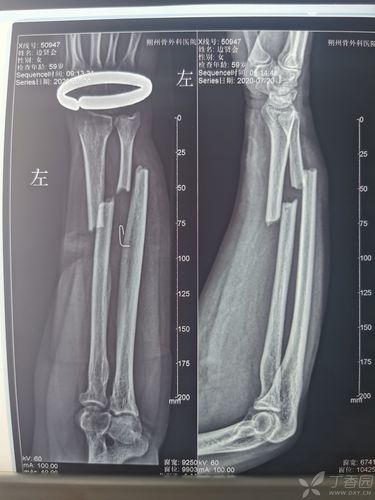

左手尺桡骨骨折图片

左手尺桡骨骨折图片,左尺桡骨骨折图片

交通事故骨折的辨别:①尺桡骨骨折(珍藏版)

尺桡骨双骨折

左尺桡骨双骨折钢板固定